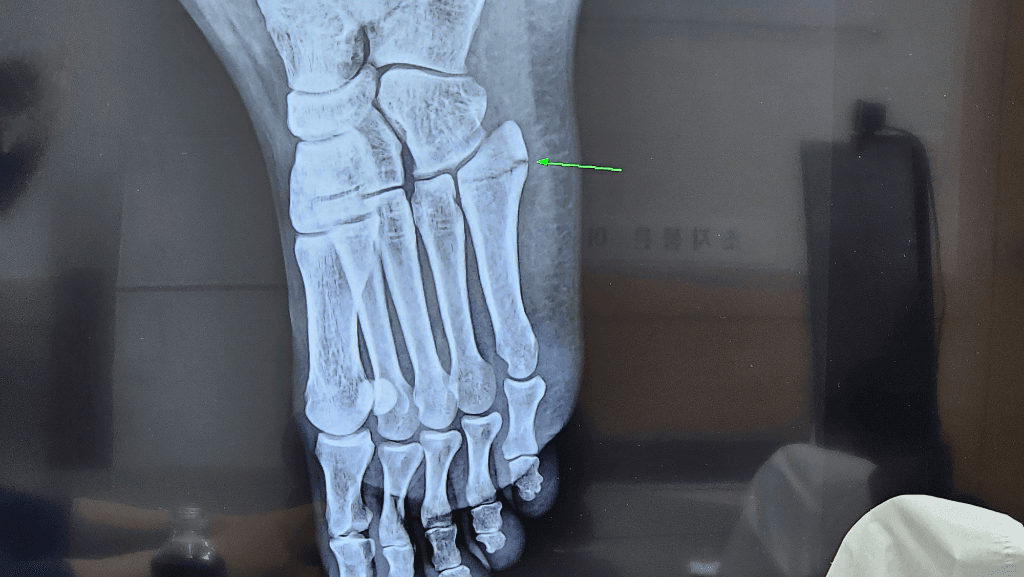

제가 길을 걷다 발을 헛디뎌서 왼쪽발 중족골5번 금이 갔는데요. 끝쪽만인건지 저 미세한 선 그어진 그거까지도 금간건지 헷갈려서요. 의사쌤께서는 끝쪽만이라는데 주변에서는 5번 선 그어진 부분 다 금간거 아니냐고해서요, 이게 엑스레이 다른 뼈랑 겹쳐서 선이 생긴건지 아님 진짜 끝쪽만인건지 궁금해서요. 현재 4주차이고요. 1주차때보다 희한하거 더 벌어진거 같고, 의사쌤도 당황하셨지만 어쨌든 사진 보시고 알려주세요

두번째 사진을 보면 중족골 base에 골절선이 길게 이어져 있는 것을 확인할 수 있습니다

첫번 째 사진보다는 훨씬 뚜렷하게 보이는 것 같습니다